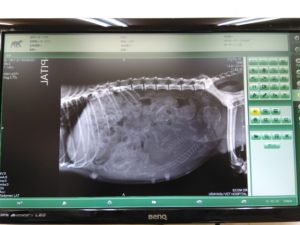

レントゲン検査

3頭の胎児を確認出来ました(・∀・)